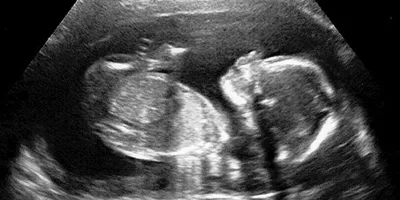

An ultrasound scan, sometimes called a sonogram, is a procedure that uses high frequency sound waves to create an image of part of the inside of the body, such as the heart. What is an ultrasound & what are they used for? Image Ultrasound scans are commonly used during pregnancy to produce images of the baby in the womb. They can also be used to: Detect heart problems Examine other parts of the body such as the liver, kidneys & abdomen Help guiding a surgeon performing some types of biopsy A small device called an ultrasound probe is used, which gives off high-frequency sound waves. You can't hear these sound waves, but when they bounce off different parts of the body, they create "echoes" that are picked up by the probe & turned into a moving image. This image is displayed on a monitor while the scan is carried out. As sound waves are used rather than radiation, the procedure is safe. Relevant Edinburgh Imaging publications 01 Feb 22. Featured Paper. Development of preclinical ultrasound imaging techniques to identify and image sentinel lymph nodes in a cancerous animal model 16 Feb 21. Featured Paper. Sonographic bridging callus at six weeks following displaced midshaft clavicle fracture can accurately predict healing. 09 Oct 18. Featured Paper. The LKB1–AMPK-α1 signaling pathway triggers hypoxic pulmonary vasoconstriction downstream of mitochondria. 29 Aug 18. Featured Paper. Evaluation of intravascular ultrasound catheter-based transducers using the resolution integral. Please view all our publications, here This article was published on 2024-08-22